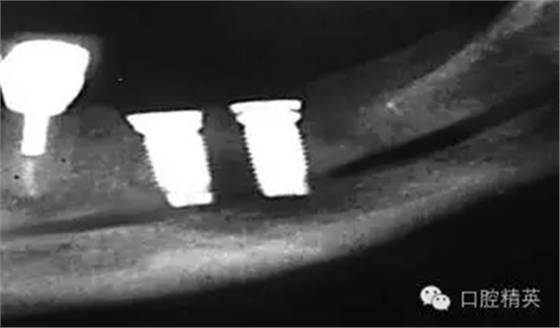

圖2b:術(shù)后斷層片顯示一顆種植體異位于右側(cè)上頜竇中,ICATCBCT顯示了種植體在上頜竇頰舌方向上的位置對(duì)于同一位點(diǎn),不同角度的圖像可以一一呈現(xiàn),將猜測(cè)拒口腔種植之門(mén)外。另外,CBCT對(duì)放射線的利用率很高,大大降低了放射劑量,它的放射劑量遠(yuǎn)遠(yuǎn)小于拍攝全口根尖片(無(wú)論是數(shù)字牙片還是膠片牙片)的放射劑量。從牙醫(yī)的角度,CBCT的應(yīng)用同樣增加了他們的利潤(rùn)。